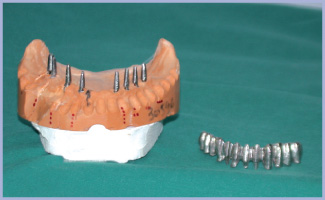

- Figg. 15, 16, 17, 18 – Monconi e sovrastrutture protesiche

- Fig. 16

- Fig. 17

- Fig. 18